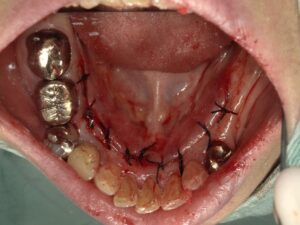

コーヌスデンチャーとは残っている歯に冠のような金属を被せてその上にさらに金属を被せる

2重の冠でできた入れ歯になります。茶筒の原理で固定されるため安定感が高く、審美性や装着感に

優れています。ドイツで開発されたテレスコープデンチャーの一種です。

画像の様なイメージになります。針金を使いませんので

見た目がよくまた維持力も大きくとても良好な義歯となります。